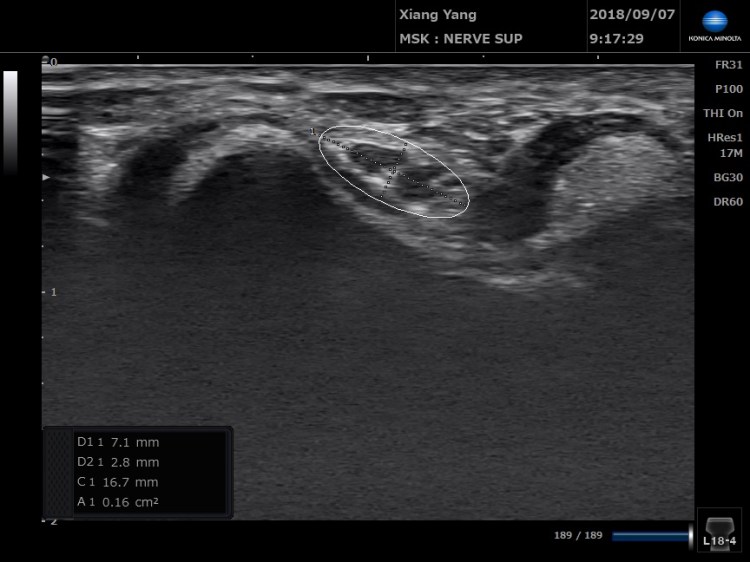

我們沿著尺神經往下掃描,發現在一開始和最後,尺神經的大小都還OK,只有在經過肘隧道的位置才比較腫大。

神經脫位,不一定會造成症狀,除非因為反覆脫位,導致第4-5指麻木,並且在肘隧道處真的有看到神經腫脹(一般來說正常值約0.10cm2)。 這時可以透過神經解套治療去解除神經腫脹的現像。治療選項還有透過增生治療強化歐氏韌帶(Osborne ligament),或是透過運動訓練減少滑車上肘肌過度活化,真的效果不彰,也可以透過手術做尺神經轉位。 請跟醫師詢問適合您的治療方式。